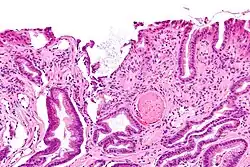

GAVE is characterized by dilated capillaries in the lamina propria with fibrin thrombi. The main histomorphologic differential diagnosis is portal hypertension, which is often apparent from clinical findings.